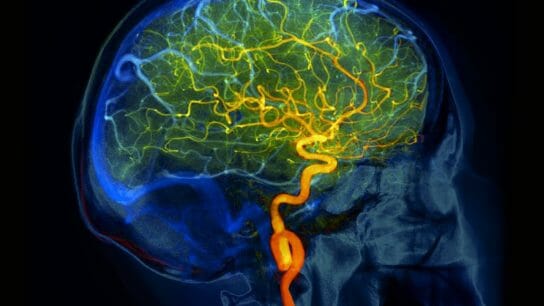

Drs Lucke-Wolde and Sun discuss the incidence of and risk factors for pediatric stroke, as well as advances and remaining gaps in the field.

Researchers examine the link between sickle cell disease and cerebrovascular incidents.

Researchers sought to highlight several recent advances in the epidemiology, pathogenesis, clinical features, investigation, acute management, and secondary prevention of cerebrovascular diseases in patients with hematological diseases.